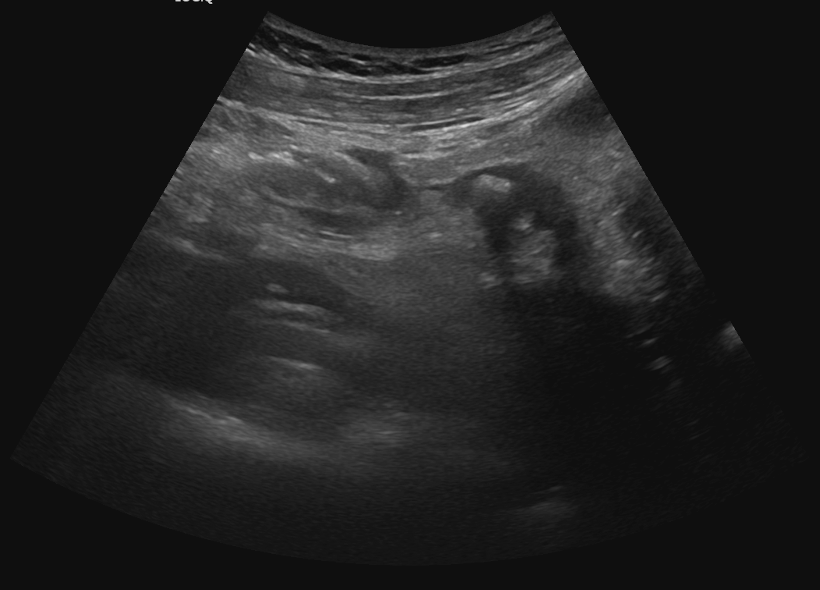

Se realiza ecografía clínica a pie de cama donde se evidencia vesícula alitiásica, Blumberg positivo con la sonda ecográfica, apéndice parcialmente visualizado con imagen hiperecogénica con sombra posterior que podría corresponder a apendicolito, sin signos de flemón.